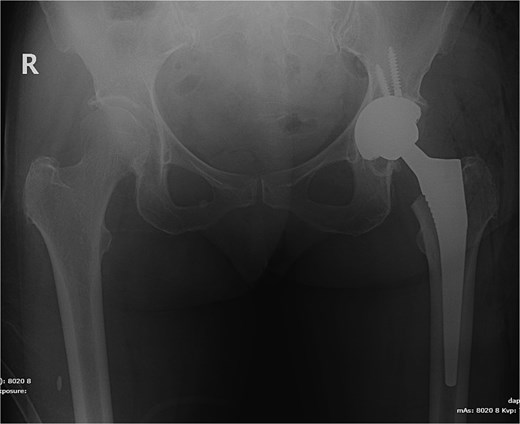

The patient underwent left total hip arthroplasty (Fig. 2). Her hospital stay was smooth and uneventful without any complications. Her wound was clean and dry without erythema or oozing and was discharged on prophylactic anticoagulation and pain medications.

X-ray pelvis showing left total hip replacement with hardware in adequate position.